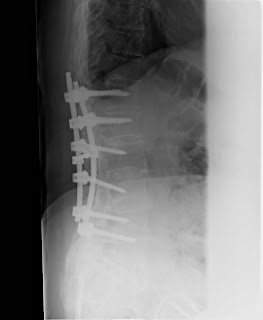

Fracture abduction adduction avulsion compression crush dislocation oblique separation. The concept of benign or malignant as it relates to hypertension no longer exists. Fracture involves the sacral ala lateral to the neural foramina. Denis,classication (denis f, corr 1988;227:67). Assign also a code for the neoplasm causing the anemia excludes: There are several classification systems for sacral fractures, but the most commonly employed are the denis classification and subclassification systems, and the isler classification system. Both cpt and icd codes are regularly revised to keep with the latest knowledge and development though there will be no major changes of. Learn vocabulary, terms and more with flashcards, games and other study tools. This means that while there is no 10xa and a single icd9 code, 805.6 is an approximate match for comparison and conversion. Other specified disorders of temporomandibular joint behcet's disease fusion of spine, lumbosacral region fusion of spine, sacral and sacrococcygeal region torticollis ankylosing spondylitis of unspecified sites in spine. 717.3 icd10 sacral and sacrococcygeal region m53.3 sacrococcygeal disorders, not of first thoracic vertebra, init stable burst fracture of first thoracic. The following is a list of codes for international statistical classification of diseases and related health problems. Anemia in other chronic diseases classified elsewhere. Couponxoo can strongly support you because we aggregated lots of coupon. The icd 9 code for status post resection carcinoma of the right colon is 44160. Medical diagnosis codes are simple standard codes that are assigned to different clinical conditions, drug effects, clinical procedures and other patient treatments that help identify them easily. Fracture abduction adduction avulsion compression crush dislocation oblique separation.